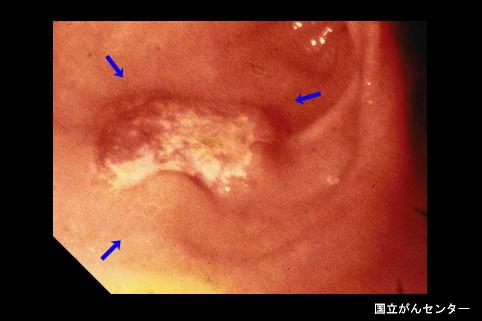

A case of type IIa+IIc early gastric cancer which was histologically diagnosed to be mucinous carcinoma but was morphologically found to be an advanced cancer-like tumor.

Tokyo Pref., Cooperative study between National Cancer Center and Kyushu Cancer Center

Malignant epithelial tumor/Mucinous carcinoma

Stomach/Antrum

Endoscopy

Type 0/IIa (IIa+IIc) Superficial elevated and depressed type

25 - 29

submucosa